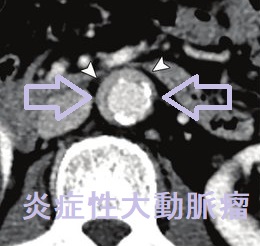

後腹膜線維症では、内臓を包む腹膜の背中側がガチガチに線維化します。腎臓から出て膀胱へ至る尿管を巻き込むため、尿の通過障害が起こります。結果、尿が腎臓へ逆流して、水腎症や急性腎盂腎炎を発症します。[Nephrol Dial Transplant. 2021 Sep 27;36(10):1773-1781.]

CT・MRIでは大動脈周囲に軟部影を認め、炎症性動脈瘤のような所見です。

IgG4 関連疾患との合併から、特発性後腹膜線維症の相当数がIgG4 関連後腹膜線維症とされます。(Intern Emerg Med. 2017 Apr;12(3):287-299.)